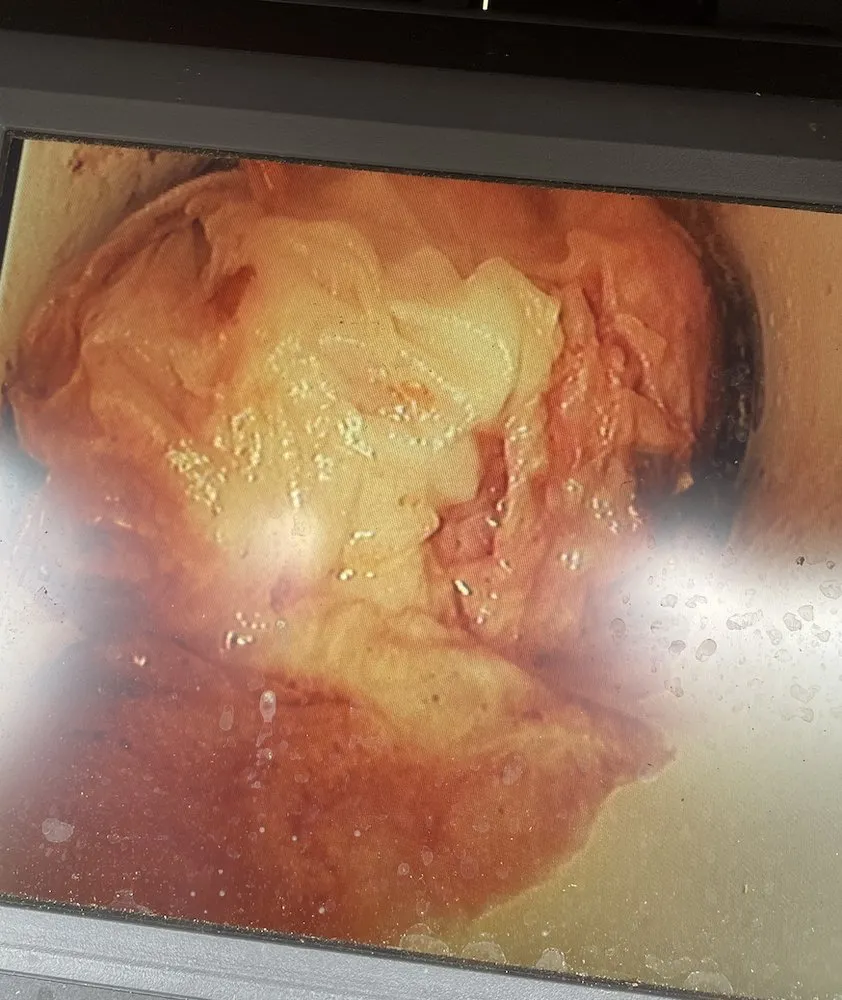

We use specialized camera inspections to pinpoint exactly where roots have breached your sewer line. For minor intrusions, high-pressure water jetting can clear the blockage and cut through the roots. For more severe or recurring cases, we may recommend a trenchless pipe lining solution, which creates a new, seamless pipe inside the old one that roots cannot penetrate. This is often a faster and less disruptive repair than traditional excavation, especially in our local sandy soil.